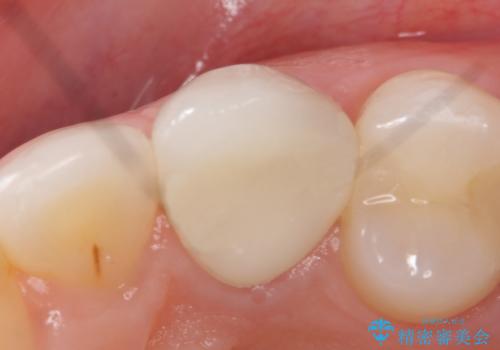

- 根管治療後歯が黄色くなってきたのでセラミックにしたいといらっしゃった方の症例です。

再根管治療後、オールセラミッククラウン(スペシャル)による補綴を行いました。